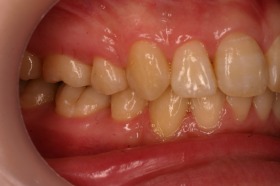

歯の矯正治療 症例ビフォー&アフター

ご覧の症例は出っ歯を矯正治療でキレイにしたケースです。

このような場合では歯を抜いて矯正するか

、抜かずに矯正するか分かれるケースです。

ご覧の矯正歯科治療の場合は、抜いて矯正歯科

治療していますが東京世田谷矯正歯科センターでは

非抜歯矯正歯科治療をベースにしています。

どうしても抜かないとキレイにならない場合のみ

抜歯して矯正歯科治療しています。